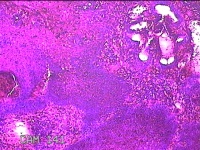

宫颈3点、6点、9点、12点组织

性别

女

年龄

38岁

临床诊断

人乳头瘤病毒感染

一般病史

发现人乳头瘤病毒感染半月。

标本名称

大体所见

1.“宫颈3点组织”:灰白暗红色组织0.8x0.7x0.2cm一块。 2.“宫颈6点组织”:灰白粉红色组织0.8x0.3x0.2cm一块。 3.“宫颈9点组织”:灰白粉红色组织0.7x0.5x0.2cm一块。 4.“宫颈12点组织”:灰白暗红色不规则碎组织1.3x1x0.3cm一堆。